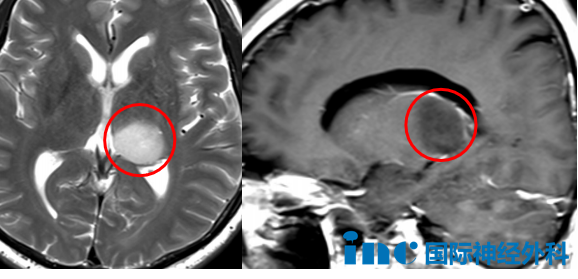

10岁的嘉嘉已经与脑子里的恶魔抗争近5年,瘦小的身躯下,是远超年龄的坚韧;而身后,是父母全身心的守护。脑干-桥臂-小脑区域占位,两次活检后,最终确诊为“儿童弥漫性星形细胞瘤(WHO 2级)”。此后,他历经多轮系统治疗,包括化疗、靶向治疗等,然而病情仍在缓慢进展。这条路,嘉嘉与家人已走了很久,每一步都不易。在期盼中,今天他们终于见到了巴教授。

“首先,此前的活检结果很可能是错误的,影像上更像是神经节细胞瘤。”这是一种起源于神经节细胞的良性肿瘤,听到这样的消息,父母又惊又喜。

“自2022年3月持续化疗至今,肿瘤体积未见缩小,说明当前化疗方案效果有限。在药物应答不明确的情况下,手术干预显得更为必要。虽然手术无法彻底治愈疾病,但能切实帮助患者——通过切除肿瘤主体,显著缓解占位效应,并阻止其继续进展。

目前肿瘤体积较大,位于脑干之外的部分有把握切除,然后尽力切除脑干内部可操作的部分。在移除大部分肿瘤后,再结合化疗。实现肿瘤大部分切除、减轻压迫,将为孩子病情的改善带来积极帮助。”

总结而言,巴教授在评估后认为,手术切除是当前控制病情、改善神经压迫的关键步骤,虽无法根治,但能为后续治疗创造更有利的条件。